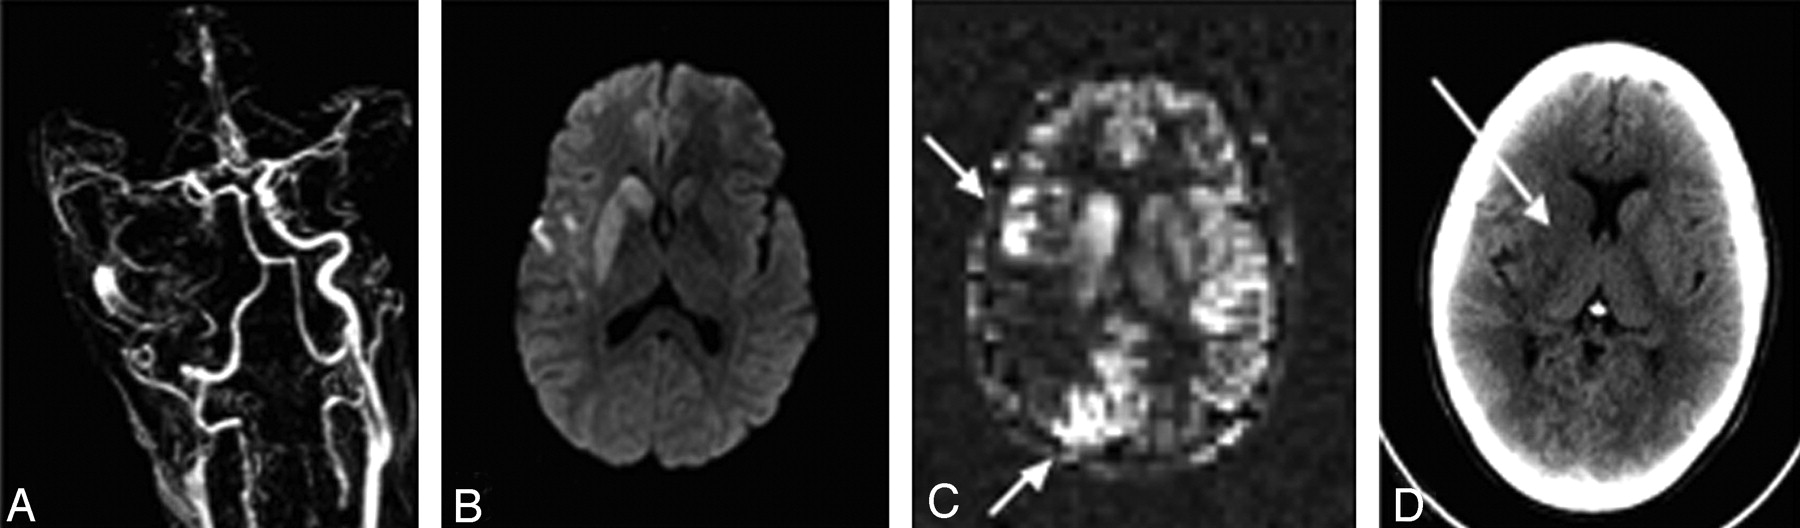

CBF quantification errors can occur due to delays in arterial arrival time (Δt), which is defined as the time between proximal labeling and subsequent extraction into the tissue at the capillary level. If arrival times were uniform and known, they could be easily corrected by including the effects of T1 relaxation within the blood upon Mart: 13) Although longer arterial arrival times would mean lower SNR images, quantification would not be affected. However, in reality, arterial arrival times are regionally dependent and difficult to measure accurately, but are typically on the order of 300–2000 ms, with the longer times seen in the white matter and vascular border zones.44 Because this is on the order of the label T1, large CBF underestimations can occur. Some investigators propose acquiring ASL difference images at different inflow times to directly estimate both Δt and CBF; however, this is usually time-consuming and the results can be confusing due to label remaining in feeding arteries during early inflow times (Fig 4) and in general leads to noisy images that are challenging to fit in a robust fashion.45 Alternatively, one can design the pulse sequence such that the labeled blood has a well-defined temporal width, which is entirely delivered to the tissue before imaging. With PASL, this is typically performed by using a variant of the Quantitative Imaging of Perfusion Using a Single Subtraction Method 2 (QUIPSS 2), in which saturation pulses applied to the labeled region permit quantitative CBF measurements during a range of expected arrival times.46

CBF errors due to prolonged arrival time in ischemic stroke with ASL. A, A contrast-enhanced MR angiogram shows right internal carotid artery occlusion. B, Diffusion-weighted image demonstrates abnormality of the right putamen, caudate, and a small area in the right frontal operculum. C, A PASL image of CBF demonstrates punctate high signal intensity (arrows) surrounding an area of apparent low flow in the right parietal lobe. The high signal intensity is probably due to delayed arrival of the label via collateral flow which is still within large vessels rather than in the parenchyma. The low measured CBF centrally is due to decay of the label before it enters the tissue. Normal flow was seen in this region on Xe-CT (images not shown). D, Follow-up CT 2 days later demonstrates infarction of the right caudate and putamen (arrow) but preserved gray-white contrast in the right parietal region that demonstrates low signal intensity on the ASL CBF map. CBF underestimation in the setting of collateral flow is a fundamental difficulty with the use of standard ASL in this patient population.